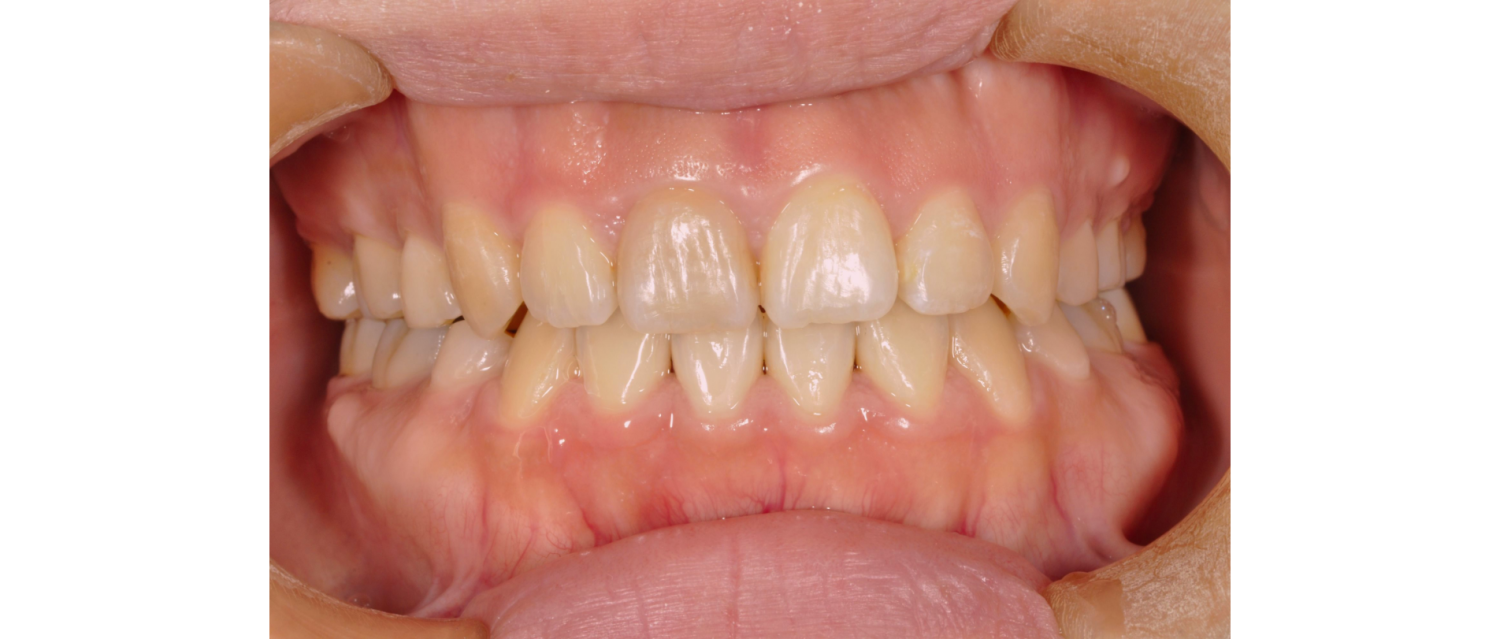

After

主訴

前歯のすき間が気になる

治療内容

矯正装置は目立たないものをご希望されておりましたので、白いブラスチックの装置(ホワイトブラケット)に対して、金属のワイヤーを通して矯正治療を行いました。

上下左右の3番目までが、白いプラスチックの装置(ホワイトブラケット)となり、6番目以降の歯は金属の装置(メタルブラケット)を使用しました。

表側矯正であっても目立ちにくい矯正装置を使うことが可能です。患者さんの様々な要望に応えられるよう努めております。